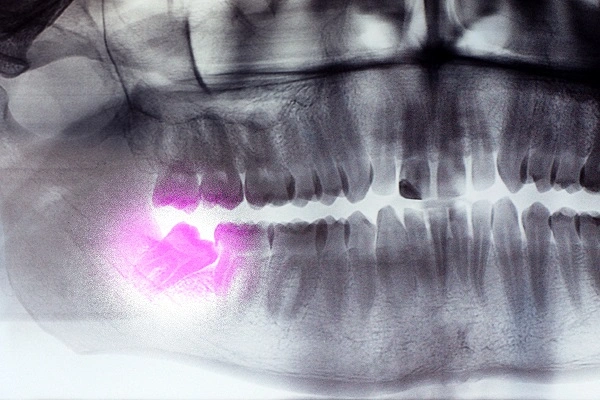

A wisdom tooth extraction is a procedure done to remove the last set of molars to emerge in the mouth. The pain, discomfort and swelling that patients experience after the procedure is part of the healing and recovery process. One question many patients ask is how long recovery takes, and this article answers that question and what recovery entails.

Wisdom teeth, also called the third molars, are the last molars to erupt. These teeth are not present in everyone; neither are they vital for a healthy, beautiful smile. However, they may become problematic if they erupt wrongly.

When these molars emerge, often between ages 16 and 20, there may not be enough space on the jaw for them to come out fully. Therefore, they may erupt at an angle, crowding the mouth and may sometimes not erupt completely. This can lead to oral health issues such as pain and infection. Most wisdom tooth removal requires a type of surgery. After the procedure, recovery starts.